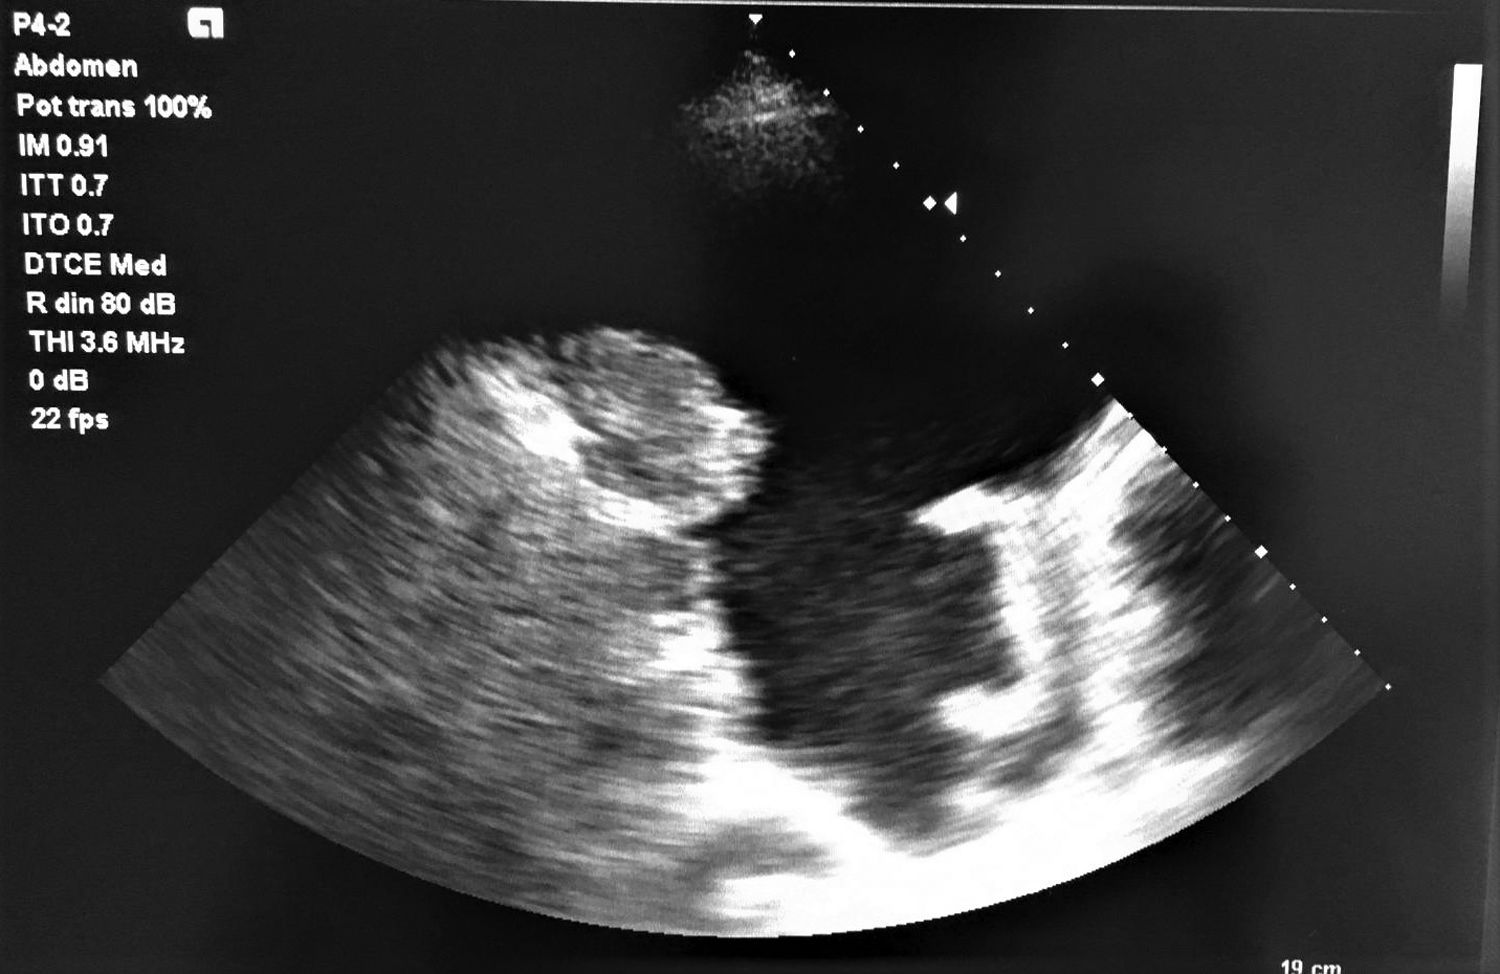

An ultrasound, also known as sonography, uses high-frequency sound waves to create live images of the inside of your body. Unlike X-rays or CT scans, it doesn't involve radiation. For mesothelioma, specifically, an ultrasound can be used to examine areas where the cancer typically develops, such as the lining of the lungs (pleura), abdomen (peritoneum), or heart (pericardium).

During the procedure, a technician applies a special gel to your skin over the area to be examined. Then, a small handheld device called a transducer is pressed against your skin and moved around. This transducer emits sound waves that bounce off organs and structures inside your body, sending echoes back to the device. These echoes are then converted into real-time images displayed on a monitor.

- Detecting Pleural Effusions: Mesothelioma often causes fluid buildup around the lungs, known as a pleural effusion. Ultrasound is excellent at identifying even small amounts of fluid and can guide its drainage.

- Assessing Lesions and Thickness: It can help visualize thickening of the pleura or peritoneum and detect any suspicious masses or lesions that might indicate mesothelioma.

- Guiding Biopsies: Perhaps one of its most critical roles is to precisely guide needle biopsies. If a suspicious area is found, an ultrasound can direct the biopsy needle to collect tissue samples for pathological analysis, ensuring accuracy and minimizing risks.